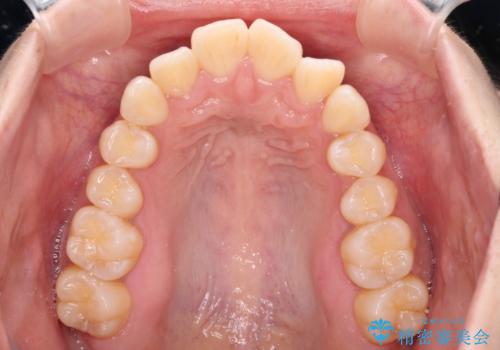

- 前歯の出っ歯と口元の閉じにくさを気にして来院された患者様です。

口元を積極的に引っ込めるために、上下左右の小臼歯4本を抜歯し、目立たないワイヤー装置にて矯正治療を行うこととしました。

上下前歯の歯軸の角度が大きく改善され、お口を閉じたときに顎先に認められた梅干し様の皺も改善されました。